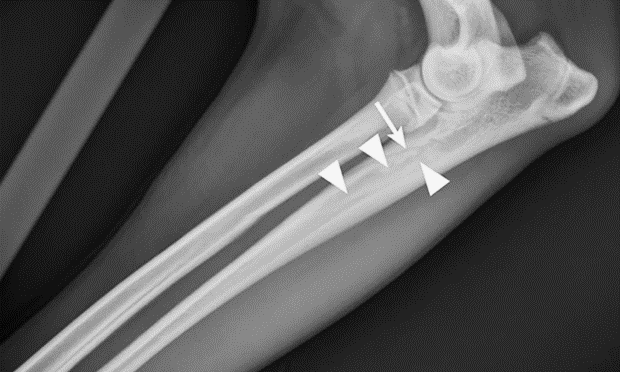

Určenie ochorenia prebieha na základe príznakov. Diagnózu potvrdzuje röntgen. V začiatku ochorenia sa vyskytuje nepatrné zvýšenie kostnej hustoty v strednej časti postihnutej kosti. V strednej fáze sa vnútro kosti stáva škvrnité, povrch kosti je drsný. V poslednej fáze je síce kosť stále škvrnitá, no pomaly sa vracia späť k normálu. .

obr.: www.cliniciansbrief.com/article/panosteitis